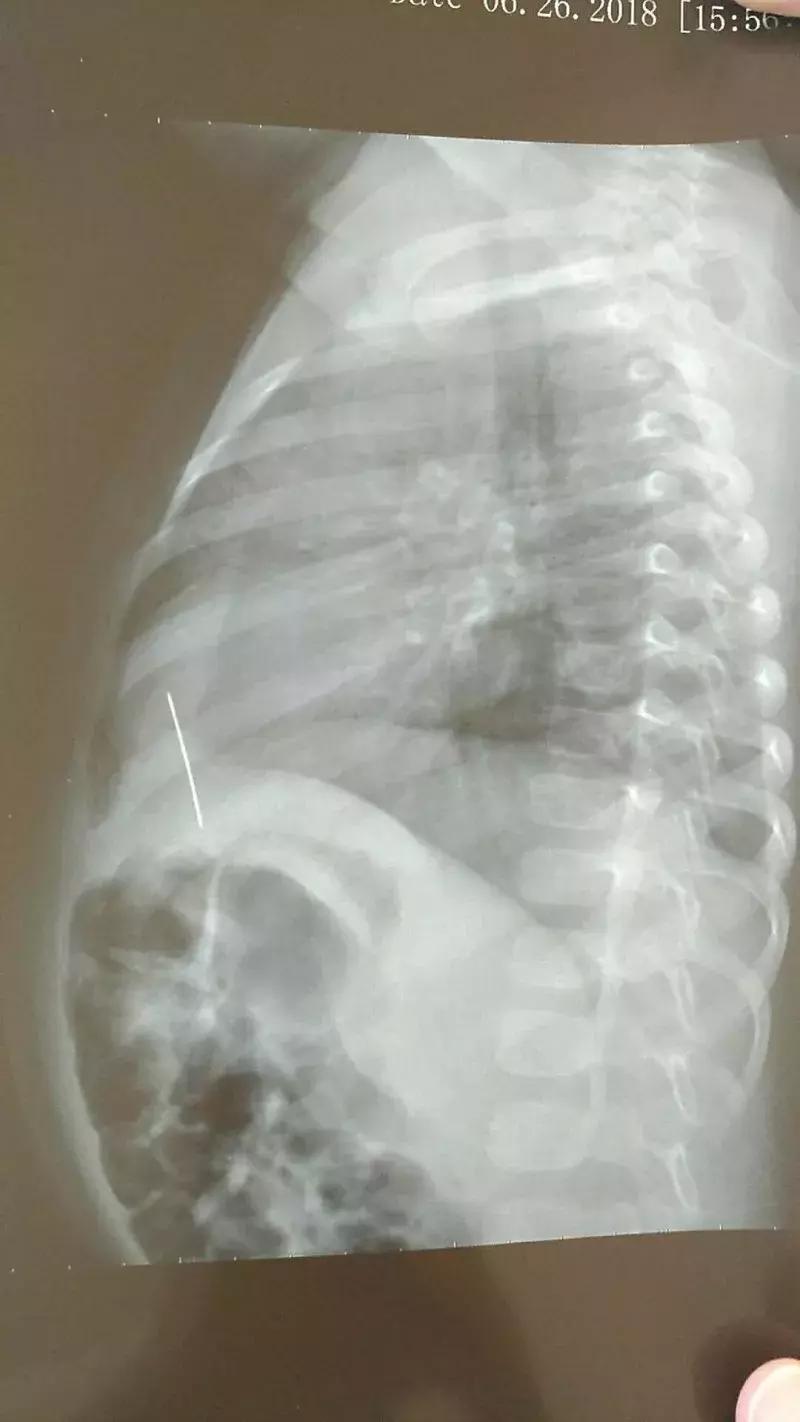

李先生忙把儿子送到当地医院,路上佳佳说,他把钉子头的那一端含在嘴里玩,一不小心就吸了进去,吞进了肚子。当地医院拍片显示,钉子确实在孩子的第一腰椎水平处。

为了尽快取出钉子,当地医生建议转往专业医院。6日,李先生和妹妹带着儿子来到武汉儿童医院就诊。

结合相关检查结果,为了避免钉子对孩子造成进一步伤害,消化内科刘医生决定当天用胃镜探查异物,尽可能取出。

当天下午,医生在胃镜下发现,胃部已经不见钉子踪影。医生继续向下查探,直到十二指肠的降部,才发现了钉子。

这说明钉子已经“游历”过食管、胃部、幽门、十二指肠球部等部位,好在这个位置,胃镜还勉勉强强可以够得到,医生顺利取出一枚约3.5厘米长的铁钉。